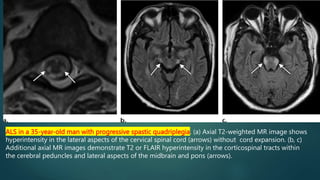

ALS in a 35-year-old man with progressive spastic quadriplegia. (a) Axial T2-weighted MR image shows

hyperintensity in the lateral aspects of the cervical spinal cord (arrows) without cord expansion. (b, c)

Additional axial MR images demonstrate T2 or FLAIR hyperintensity in the corticospinal tracts within

the cerebral peduncles and lateral aspects of the midbrain and pons (arrows).